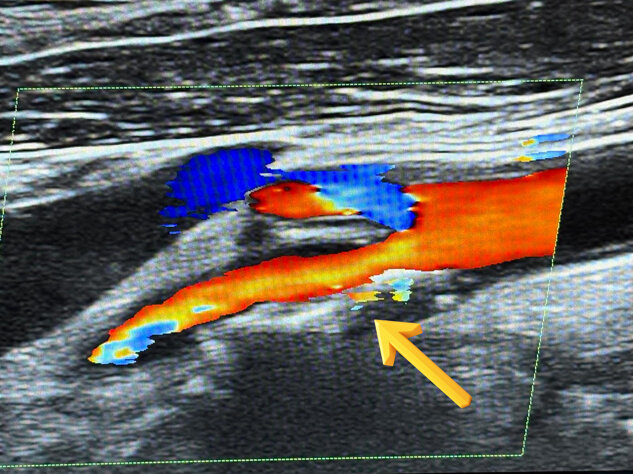

Pseudoaneurisma iatrogeno dell’arteria femorale comune post-cateterismo